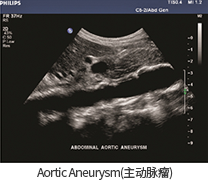

• Aortic Aneurysm(대동맥류)